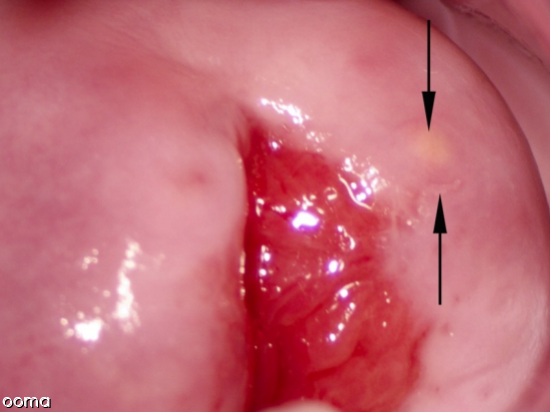

کیست های نابوتین وقتی تشکیل می شوند که غدد تولید کننده مخاط در دهانه رحم شما با سلول های پوستی پوشانده شده و مسدود می شوند. سلول های پوستی غددی را که باعث آزادسازی مخاط می شود را مسدود و آن را به کیست تبدیل می کند. این کیست ها بصورت برجستگی های کوچک و سفید رنگ هستند.

اندازه کیست های نابوتین متغیر بوده و معمولا از چند میلی متر تا 4 سانتی متر هستند. آنها صاف بوده و به رنگ سفید یا زرد به نظر می رسند. پزشک شما ممکن است در طی یک معاینه معمولی لگن متوجه یک یا چند کیست شود. این کیست ها باعث درد، ناراحتی یا علائم دیگری نمی شوند، بنابراین احتمال دارد که پزشک هنگام بررسی دهانه رحم شما برای سایر مشکلات، وجود این کیست ها را نیز تشخیص دهد.

پزشک شما همچنین می تواند از کولپوسکوپی برای تشخیص دقیق این کیست ها استفاده کند. در این آزمایش ناحیه دهانه رحم توسط یک مانیتور و دیتگاه مخصوصش چندین برابر بزرگ تر نشان داده می شود و برای تشخیص کیست های نابوتین از انواع دیگر کیست ها می باشد.